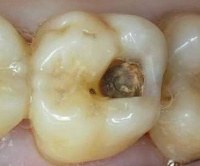

Внешние признаки включают пигментацию эмали около края печати, часто в форме края. Печать также может изменить цвет. Зуб становится сероватым, через эмаль просвечивает измененный дентин. На резцах эти изменения замечены раньше, чем на молярах. Иногда наблюдаются трещины и сколы зубной эмали и пломб. С серьезными дефектами подвижность печати может быть обнаружена; Если кариес развивается в течение длительного времени, а полость увеличена, пломба может выпасть. Бактериальный налет накапливается в трещинах, что приводит к неприятному запаху изо рта.

• Зонд попадает в зазор до глубины дентина, исследование может сопровождаться болевыми симптомами при прикосновении к дентину. Боль является признаком разрушения эмали и обнажения дентина, что указывает на большую кариозную полость.

• Сколы на сальнике, его подвижность, он может упасть частично. Зуб сильно поврежден, можно предполагать осложнения кариеса в виде пульпита.